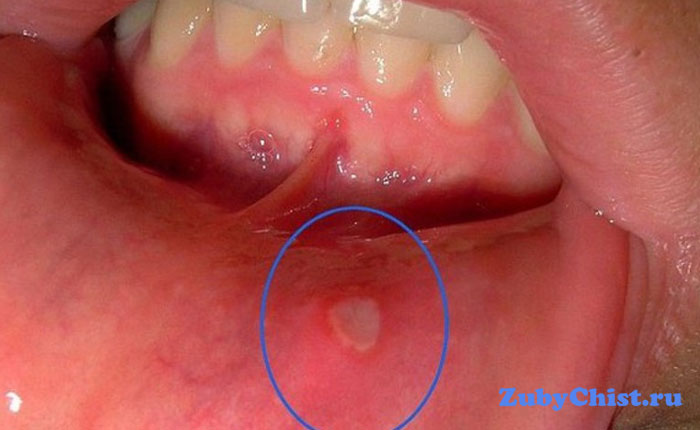

- При афтозном стоматите на слизистой появляются афты, маленькие язвочки диаметром до 5 миллиметров. Сначала появляются неплотные прозрачные пузырьки, которые вскоре лопаются, а на их месте остаются белесые поражения с красными краями. Возможно ухудшение самочувствия и повышение температуры. Язвочки очень болезненные, мешают есть и разговаривать. В случае наследственного характера вылечить стоматит во рту бывает крайне трудно. Афты вызывают вирусные инфекции, аллергия или заболевания ЖКТ.